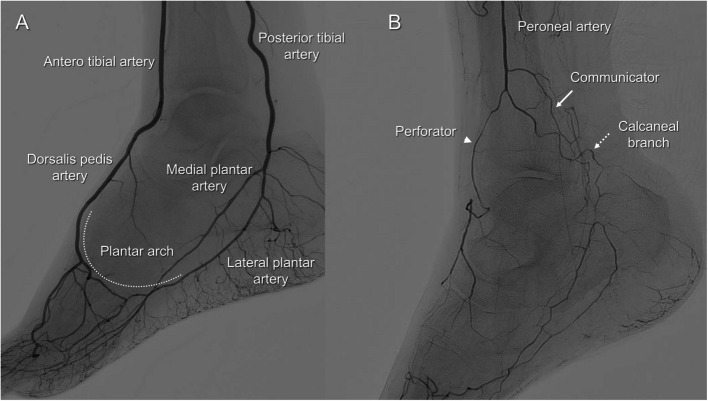

Background: Endovascular therapy (EVT) has become a key revascularization strategy for patients with chronic limb-threatening ischemia (CLTI), especially in cases involving infrapopliteal (IP) chronic total occlusions (CTOs), which are often challenging to treat using standard antegrade approaches alone. Trans-collateral angioplasty (TCA) is a retrograde technique that accesses the distal true lumen via collateral vessels when conventional methods are unsuccessful. However, clinical evidence regarding the efficacy and safety of TCA remains insufficient. This study aimed to evaluate the efficacy and safety of TCA as a retrograde approach during EVT for IP CTO lesions.

Results: This retrospective single-center study included 44 IP CTO lesions in patients who underwent TCA between January 2020 and December 2022, after excluding 18 lesions treated solely with the pedal-plantar loop technique. The mean patient age was 78.8 years, and 81.8% had diabetes, 79.5% had chronic kidney disease, and 31.8% were on dialysis. EVT success was achieved in 95.5% (95% CI: 84.9-98.7) of lesions. TCA alone achieved lesion crossing in 70.5% (95% CI: 55.8-81.8), while distal puncture was required in 13.6% (95% CI: 6.4-27.0) of cases. Various crossing techniques, including the rendezvous technique and reverse subintimal tracking, were conducted. Collateral vessel-related complications occurred in 11.3% (5 lesions; 95% CI: 5.0-24.6), including injury in 6.8%, and occlusion and spasm in 2.3%. No vessel dissections occurred. The overall incidence of perioperative complications within 30 days was 20.5% (95% CI: 11.3-34.2), most commonly gastrointestinal bleeding and stroke. At one year, the rate of freedom from target lesion revascularization was 45.4%, and amputation-free survival was 84.0%.

Conclusions: Our findings suggest that TCA can be a feasible and relatively safe retrograde strategy for complex IP CTO lesions when antegrade wiring fails. It is associated with high procedural success and a low incidence of collateral vessel-related complications, supporting its use in selected cases of CLTI.